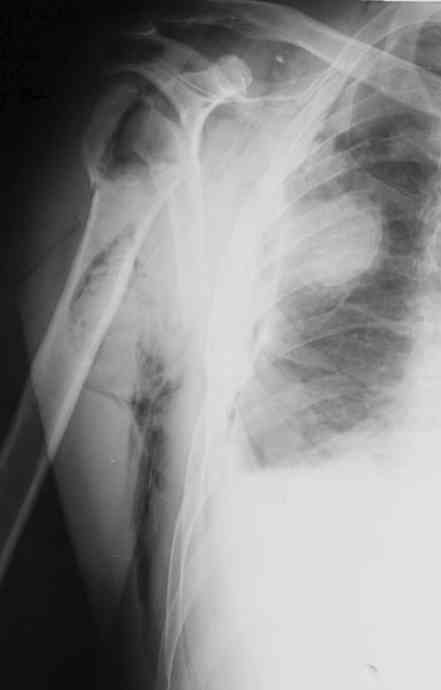

Уважаемые коллеги. Недавно из нашего отделения был выписан пациент 54 лет с закрытым переломом плечевой кости. Из анамнеза: за 2 дня до поступления в НИИСП, в состоянии алкогольного опьянения упал с лестницы на даче (высота 3-4 метра) с упором на правую руку. Через двое суток обратился за медицинской помощью. Доставлен бригадой "Скорой помощи".Правый плечевой сустав умеренно деформирован. По внутренней поверхности плеча имеется кровоподтек. При пальпации плечевого сустава имеется умеренная болезненность. Активные и пассивные движения болезненные. Снижена чувствительность по тыльной поверхности пальцев кисти и отсутствует активное разгибание кисти и пальцев. Имеется подкожная эмфизема шеи, верхней половины грудной клетки (рис 1, 2). На рентгенограмме: оскольчатый перелом головки плечевой кости со значительным смещением, перелом 2-3 ребер справа, тканевая эмфизема (рис 3). КТ при поступлении: перелом головки плечевой кости в области анатомической шейки со смещением отломка головки в грудную полость, правосторонний гидроторакс, перелом 2-3-4 ребер справа. (рис 4). Через двое суток после поступления выполнена операция: атипичная торакотомия, эвакуация свернувшегося гемоторакса, удаление инородного тела (головки плечевой кости) из плевральной полости (при этом выявлено имеющееся повреждение париетального и висцерального листков плевры) (рис. 5), дренирование плевральной полости, замещение проксимального конца плечевой кости спейсером из костного цемента с антибиотиком (рис. 6). Послеоперационный период протекал гладко. При контрольной рентгенографии положение спейсера удовлетворительное (рис. 7, 8). Дренаж из плевральной полости удален через 3 суток после вмешательства. Послеоперационная рана зажила первичным натяжением. Через 12 дней после операции больной выписан на амбулаторное лечение.

Я абсолютно согласен с Вами. Бугорки мы не выделяли и не фиксировали. Дело в том, что основная линия перелома проходит по анатомической шейке. И ниже нее кость повреждена, но существенного смещения осколков и бугорков до и во время операции не отмечено (прилагаю первичный снимок лучшего качества - рис. 1).